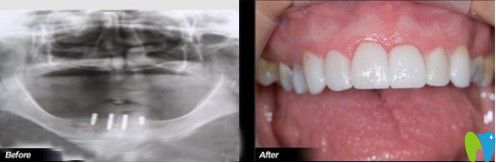

想了解沈陽(yáng)歡樂(lè)仁愛(ài)口腔做種植牙的效果如何?我們一起來(lái)瞧一瞧何先生做過(guò)種植牙之后案列吧!

何先生做過(guò)種植牙的案列圖

癥狀描述:何先生,46歲,因?yàn)檠乐軉?wèn)題引起多顆牙松動(dòng),后來(lái)導(dǎo)致全口牙脫落。開(kāi)始,何先生一直佩戴活動(dòng)假牙,但是很影響咀嚼和消化,長(zhǎng)期如此身體健康也受到了影響。

歡樂(lè)口腔醫(yī)生診斷:上下牙列缺失,全口牙齒只剩下上牙中一顆虎牙。

歡樂(lè)口腔治療方案:根據(jù)顧客的口腔內(nèi)部需求,決定植入4顆種植體,然后做覆蓋義齒修復(fù)。